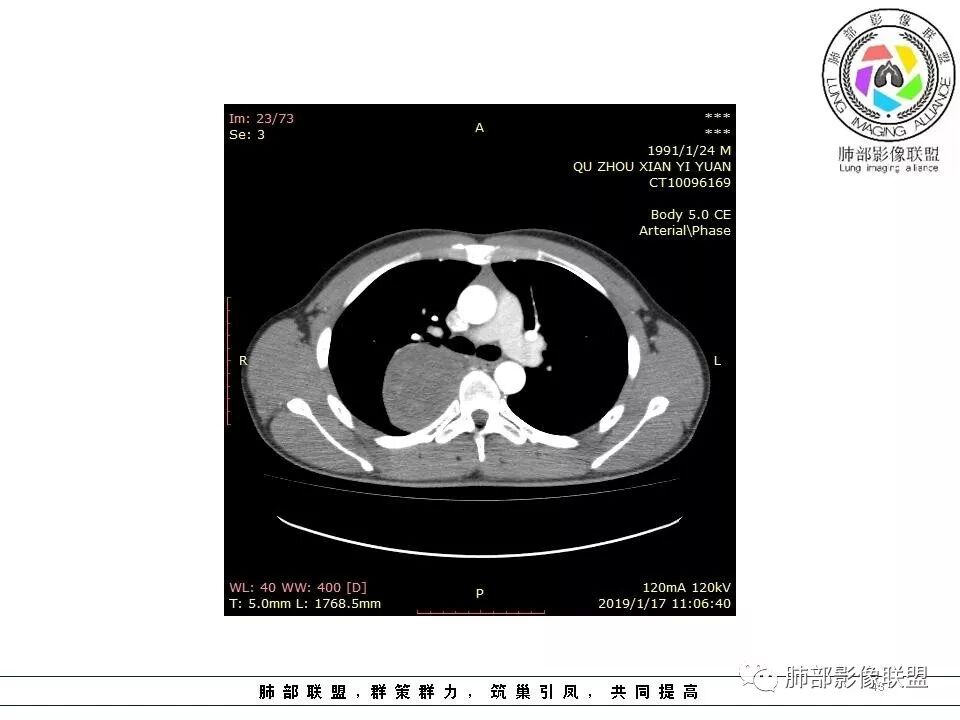

脏层胸膜主要由支气管动脉和肺动脉供血,壁层胸膜主要由支气管动脉,胸廓内动脉、肋间动脉供血

如果是肋间动脉,就不可能是脏层胸膜,可以是壁层或者纵膈

但是这个病人,肋间动脉供血吧,我倾向胸膜

管洪林:

看血供来源(体循环),脏层来源需要打个问号了

边缘光滑,宽基底与胸壁相连,跨叶裂,叶裂稍前推,血管、支气管前移。

浅分叶

外上侧少量胸水

肋间动脉供血,强化尚均匀,逐步强化

供血,体外供血,体循环,要么是壁层胸膜,要么胸膜外的,脏层胸膜应该是对内供血。病变里面的血管,除非是非常粗大迂曲的血管,不然,我不认为是其特点。

脏层胸膜肺内供血,壁层胸膜体外供血

肺外要多考虑一下了